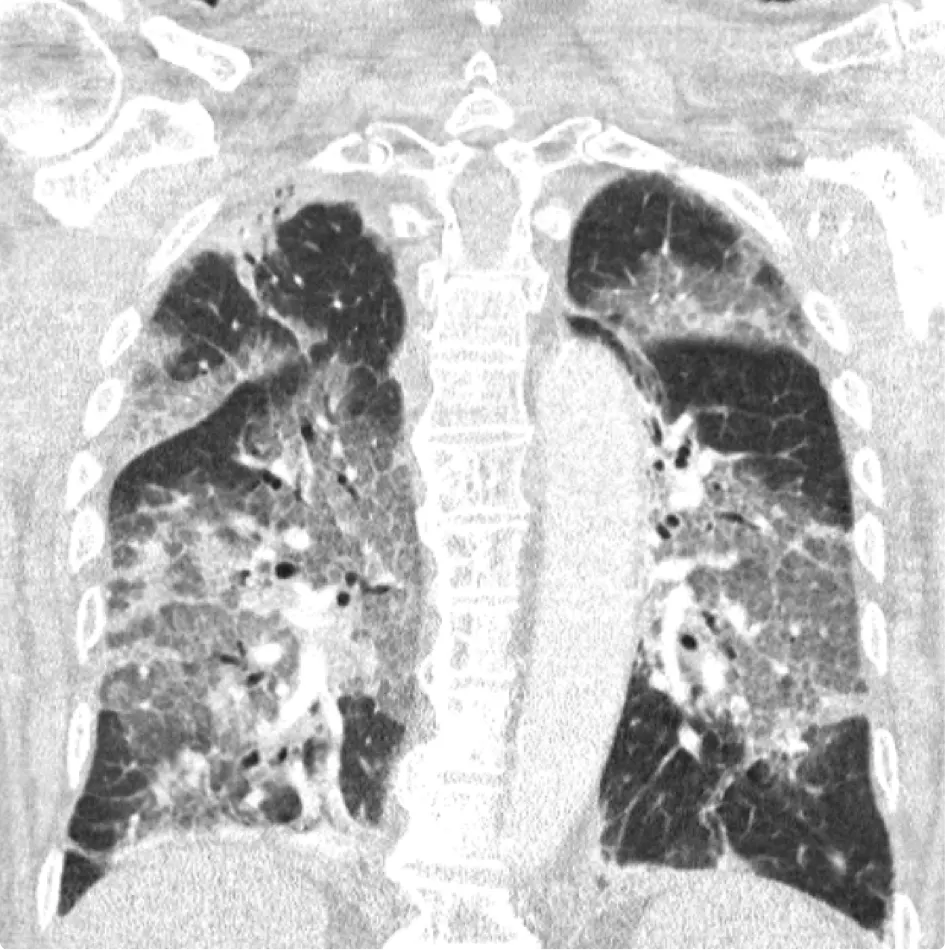

Het Zuyderland ziekenhuis deelt dit weekend een longfoto van een coronapatiënt die moest worden opgenomen in het ziekenhuis, nadat hij eerder het AstraZeneca-vaccin had geweigerd.

Met instemming deelt het ziekenhuis nu zijn longfoto, in de hoop een krachtig signaal af te geven tegen 'het vaccinatie-zwabberbeleid' van de minister. "Wilt u alstublieft stoppen met dralen en onrust zaaien, met insinueren dat u veiligheid biedt door alles eerst goed uit te laten zoeken? De cijfers die de voordelen van massavaccinatie aantonen zijn overweldigend. Ze liegen echt niet", luidt het statement van het ziekenhuis. "Laten we dan landelijk de maximale vaart erin brengen!"